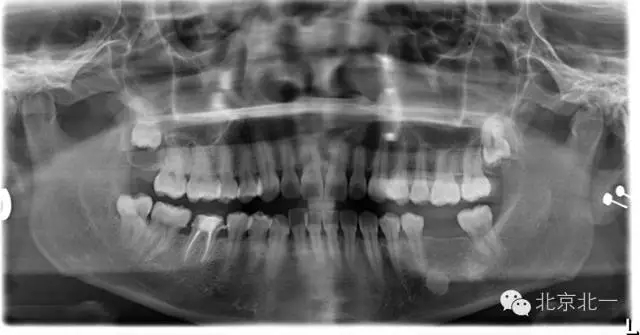

先看一例病例。頜骨內(nèi)單發(fā)高密度影像。是什么?能不能影響種植, 骨島是什么鬼?需要怎么處理?

根尖片顯示D6深齲,根尖低密度區(qū)周圍骨小梁增粗、增多,骨質(zhì)密度增高,骨髓腔變小(黑色箭頭)。

右下頜C4根尖區(qū)課件一類圓形高密度影,與周圍骨質(zhì)分界清晰,C4牙周膜影像連續(xù)、完整,下頜骨未見膨隆。